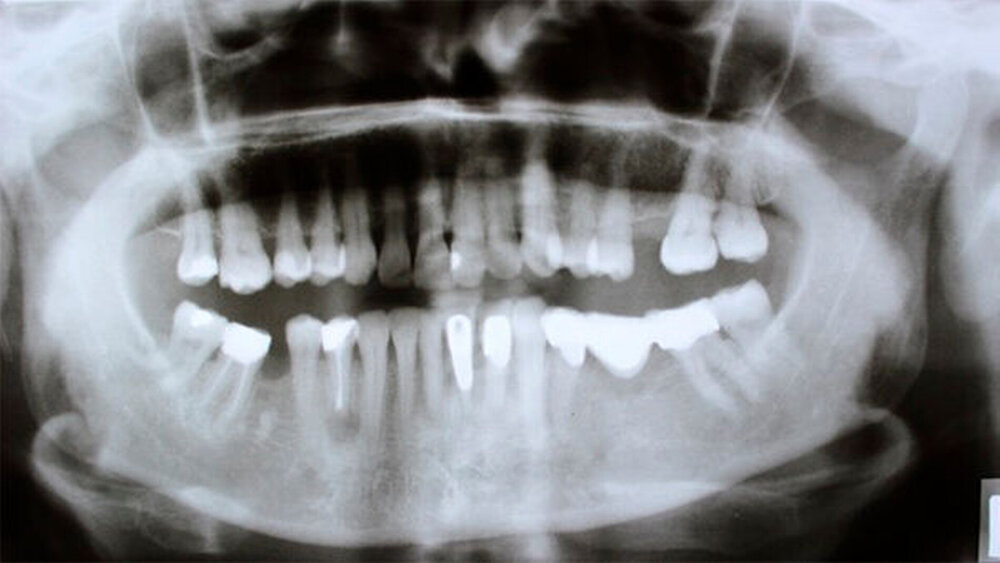

Die radiologische Diagnostik ergab keine dentalen und ossären Auffälligkeiten im Hinblick auf den intra- und extra-oralen Befund. Neben einer unklaren knöchernen Verschattung regio 046 sowie einer unversorgten Schaltlücke regio 026 zeigte sich auch klinisch ein kariesfreies Gebiss.